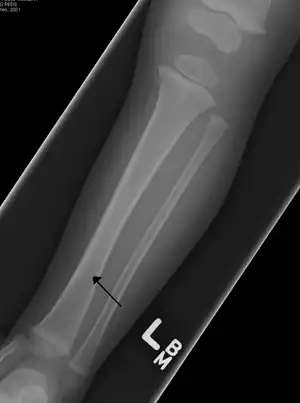

Toddler's fractureToddlersundisplaced spiral fracture of distal tibia in children under 8 years oldlow-energy trauma, often rotationalThe toddler's fracture revisited Archived 2016-03-03 at the Wayback Machine at Wheeless' Textbook of Orthopaedics online